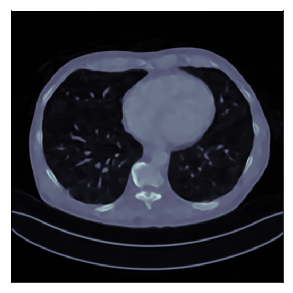

We consider the variational reconstruction framework for inverse problems and propose to learn a data-adaptive input-convex neural network (ICNN) as the regularization functional. The ICNN-based convex regularizer is trained adversarially to discern ground-truth images from unregularized reconstructions. Convexity of the regularizer is desirable since (i) one can establish analytical convergence guarantees for the corresponding variational reconstruction problem and (ii) devise efficient and provable algorithms for reconstruction. In particular, we show that the optimal solution to the variational problem converges to the ground-truth if the penalty parameter decays sub-linearly with respect to the norm of the noise. Further, we prove the existence of a sub-gradient-based algorithm that leads to a monotonically decreasing error in the parameter space with iterations. To demonstrate the performance of our approach for solving inverse problems, we consider the tasks of deblurring natural images and reconstructing images in computed tomography (CT), and show that the proposed convex regularizer is at least competitive with and sometimes superior to state-of-the-art data-driven techniques for inverse problems.